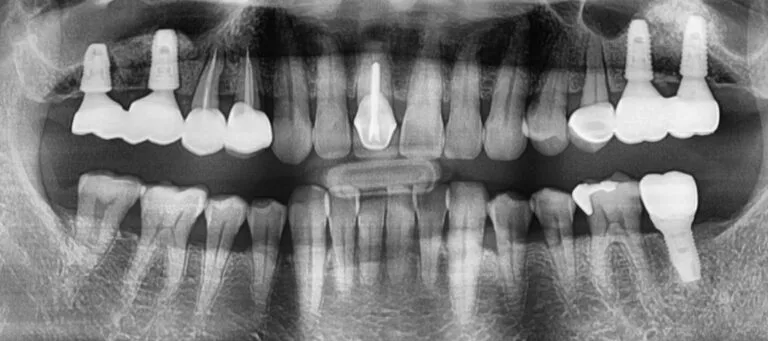

After the six-month healing period, we proceeded with the second stage, uncovering the implants and beginning the prosthetic phase. As with complex cases, we started with temporary crowns to assess the shape, color, and bite, ensuring his comfort and satisfaction before creating the final restorations. After a month of testing, we fabricated the permanent crowns. While the temporary phase is time-consuming, it ensures optimal results in both function and aesthetics.

The process didn’t end there. We meticulously fine-tuned the final crowns, scheduling follow-up appointments to make necessary adjustments. Unlike natural teeth, which can adapt over time, implants are fixed and require precise adjustments for a perfect fit.

Today, he is delighted with his new teeth, and we have entered a maintenance phase to ensure their long-term success.